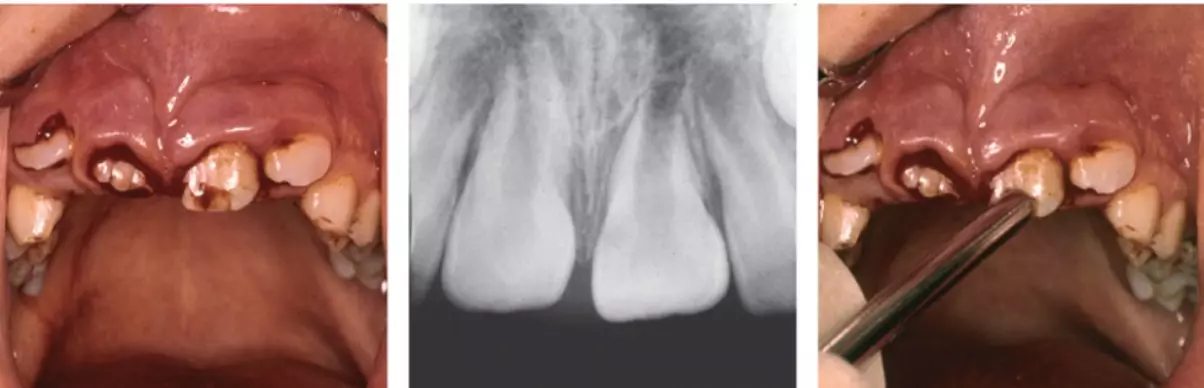

Травмы молочных зубов у детей – не редкость, в особенности у малышей в возрасте 1-3 лет. Своевременное обращение к детскому стоматологу в NikaDent и правильные действия в первые минуты после получения травмы позволяют сохранить зуб ребенка, дождаться его физиологической смены впоследствии.